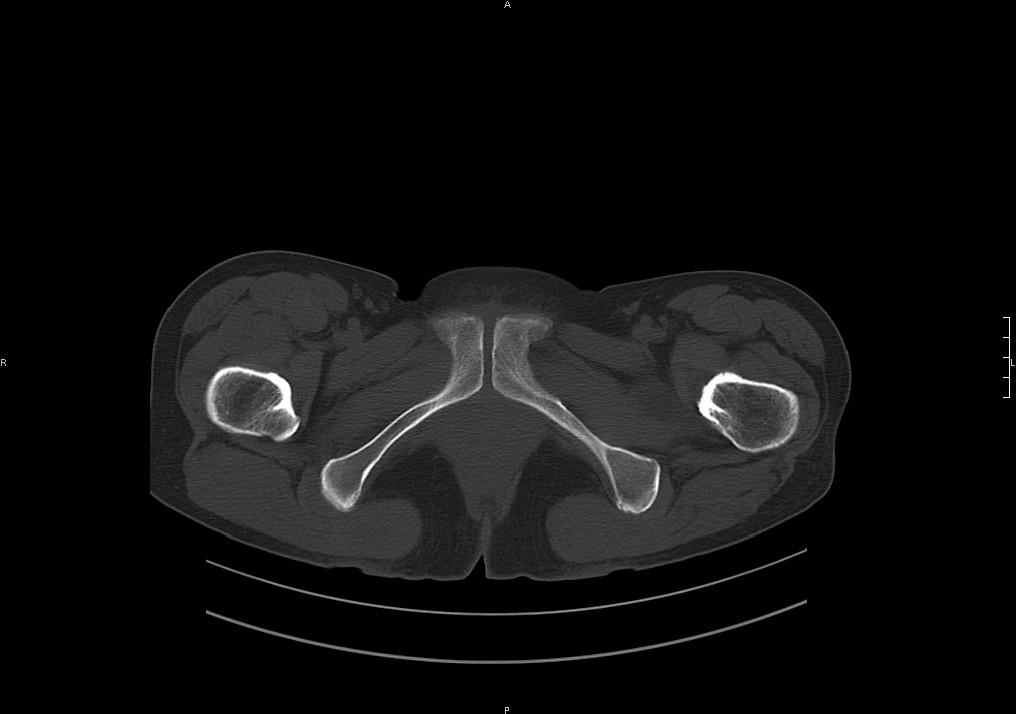

标题: CT19780左髋关节疼痛伴跛行1年,加重1个月。无菌性坏死? [打印本页]

标题: CT19780左髋关节疼痛伴跛行1年,加重1个月。无菌性坏死?

左髋关节内内可见关节鼠及滑囊积液.

考虑为滑膜骨软骨瘤病.

滑膜增厚钙化,关节鼠及滑囊积液,髋臼增生。考虑骨性关节病

髋臼平浅,股骨头覆盖率减小,考虑双侧髋关节发育不良伴退行性变。

股骨颈陈旧性骨折

髋关节退行性骨关节病